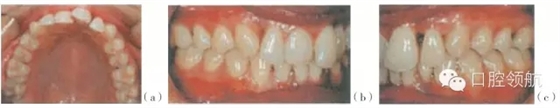

牙齒移位是牙周骨組織支持減少和臨床附著喪失的結(jié)果?;颊呓?jīng)常抱怨前牙出縫,切牙不在牙弓的弧線上,傾斜或旋轉(zhuǎn)(圖29.4,圖29.5)。這些現(xiàn)象在慢性牙周炎患者中發(fā)生相對緩慢。但是,在侵襲性牙周炎患者中或存在危險因素時,發(fā)生更快一些,咬合因素也起到一定的作用。

圖29.4 (a~c)有局限型侵襲性牙周炎病史的28歲的女性患者(不吸煙),之前進行過牙周治療,左上中切牙及左下側(cè)切牙有炎癥。左下中切牙已有移位,不在牙弓的正?;【€內(nèi),出現(xiàn)傾斜及旋轉(zhuǎn)